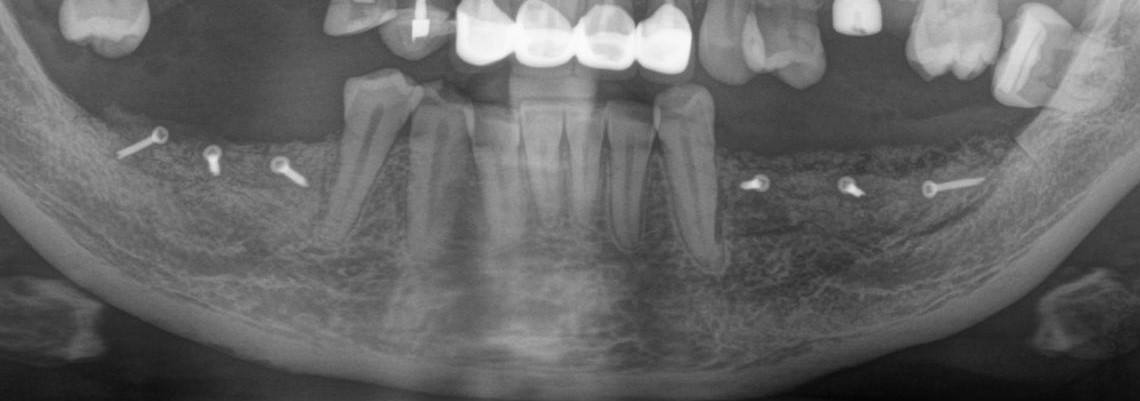

Рентгеновский снимок после операции (расщепление было проведено с двух сторон):

Снимок, сделанный через 5 месяцев после операции:

Обратите внимание, как изменился цвет кости. Она полностью восстановилась. На снимке этот участок стал белее.

Рентгеновский снимок после имплантации:

И спустя 3.5 месяца на этапе временных коронок (коронок не видно потому, что материал, из которого они изготавливаются, не рентгеноконтрастен):

Пиздюк в лице горизонтального зуба мудрости (на снимке справа) успешно был удалён.